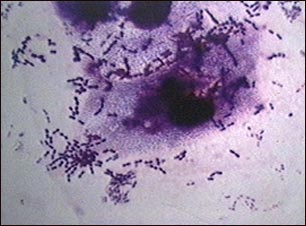

Clínica: La erupción se caracteriza por la aparición de una mácula-pápula (granito rojo) que posteriormente se transforma en vesícula con líquido transparente que después se transforma en turbio y finalmente se seca en forma de costra de color marrón. Les lesiones aparecen en cara, abdomen o espalda y después se extienden por todas partes del cuerpo (cuero cabelludo, boca, nariz, orejas y genitales). Suelen haber 3 erupciones en días consecutivos. Estas lesiones provocan picor, en ocasiones importante.

Diagnostico:Es clínico, es decir las lesiones de la piel son típicas.